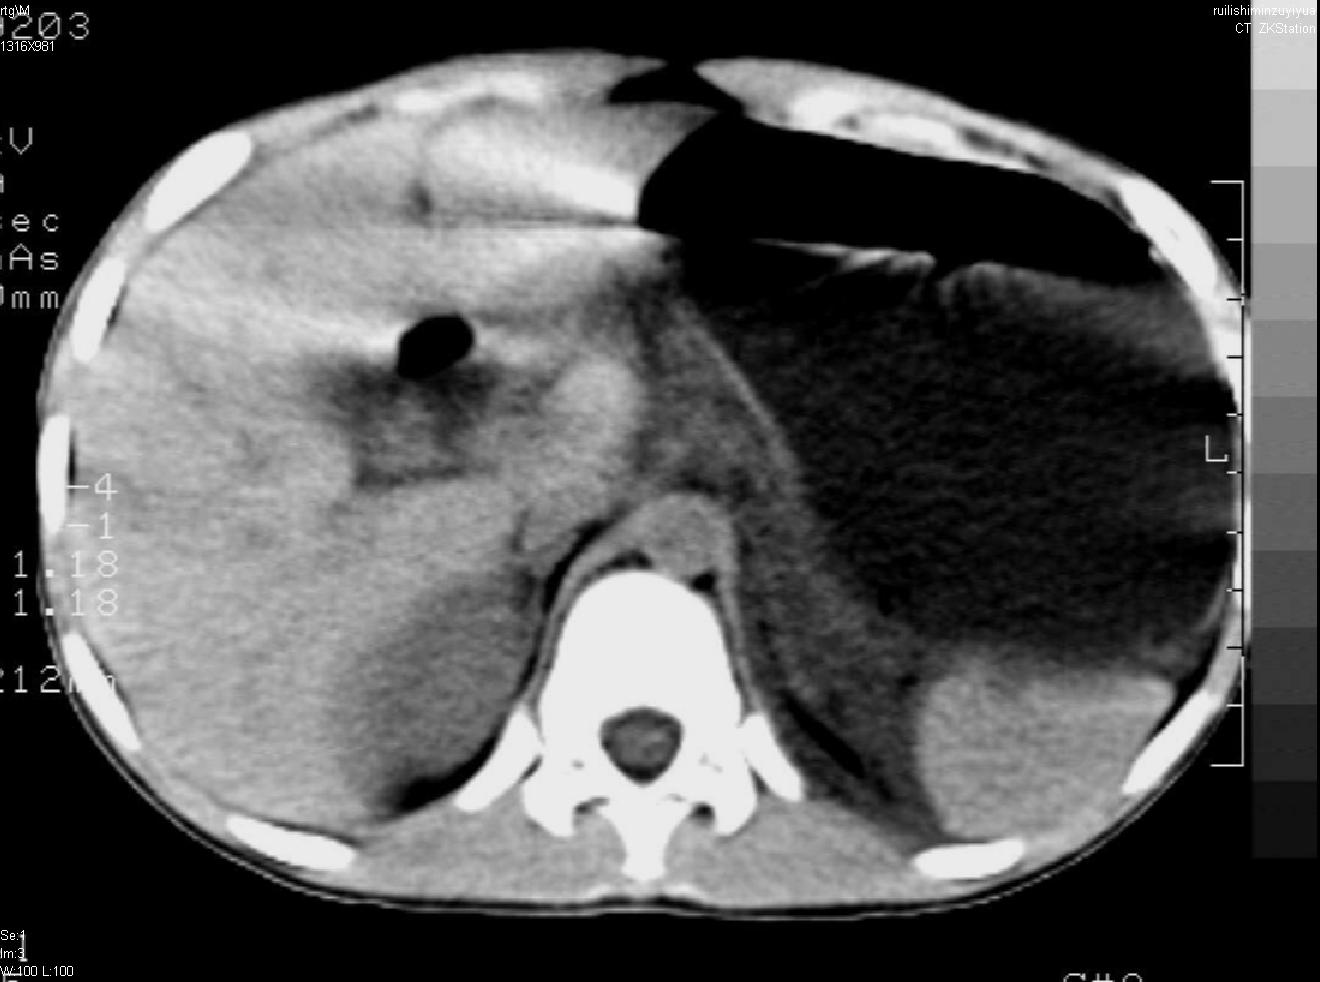

标题: PED0282:女,10岁,上腹疼痛2周 [打印本页]

标题: PED0282:女,10岁,上腹疼痛2周

b超:胆囊结石。疑坏死性胰腺炎

支持小儿急性坏死性胰腺炎。

支持急性胰腺炎。

支持急性胰腺炎并腹膜炎。

急性胰腺炎,腹腔积液